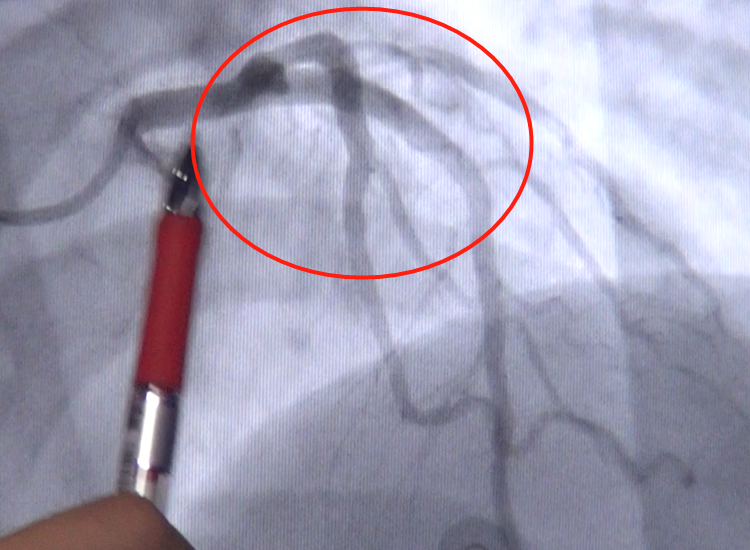

支架置入前前降支病变处!

手术前照片(前降支)

"这个患者的前降支近段严重狭窄,需要植入支架治疗.